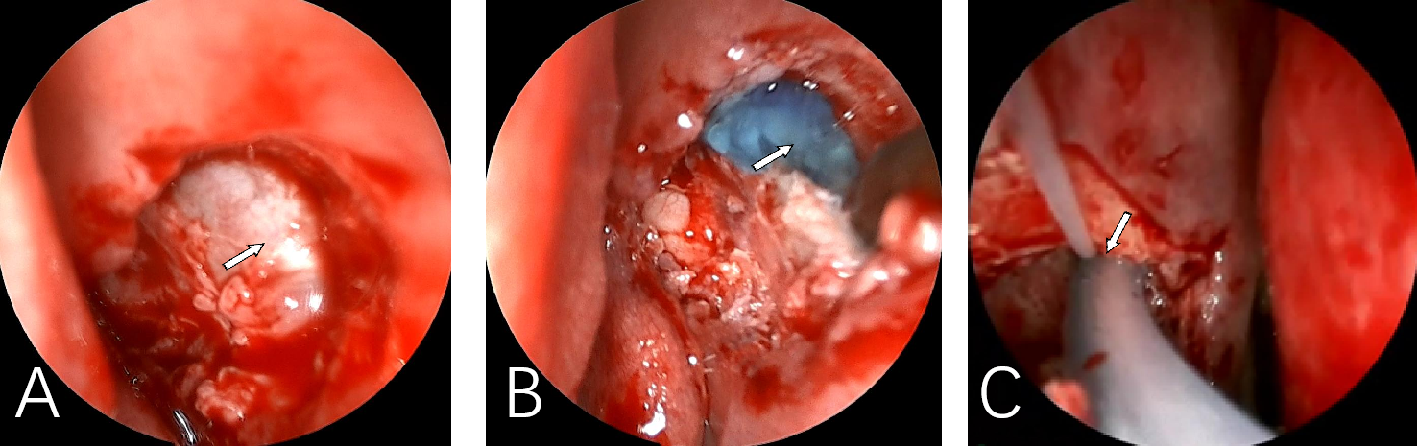

研究组(A组)采用低位经鼻内镜泪囊鼻腔吻合联合新型RT人工泪管置入术:2%利多卡因鼻腔黏膜下浸润麻醉,于中鼻甲腋外上方,用咬骨钳咬掉鼻腔外侧壁骨质,造一直径为1 cm的骨孔,充分暴露泪囊内侧壁。用镰状刀弧形切开下1/4~1/3泪囊内侧壁,呈“П”字形切开。修剪鼻腔黏膜,将泪囊瓣翻向鼻腔黏膜瓣,使两瓣的边缘对合在一起。经鼻腔置入RT人工鼻泪管并双泪小管置入式人工泪管,支撑吻合道(图1、2)。对照组(B组)采用常规经鼻内镜泪囊鼻腔吻合联合双泪小管置入式人工泪管置入术(图3):2%利多卡因鼻腔黏膜下浸润麻醉,于中鼻甲腋外上方,用咬骨钳咬除上颌骨鼻突及泪骨骨壁(在骨质较厚且硬的患者需借助骨钻),造一直径为1 cm的骨孔,充分暴露泪囊内侧壁。用镰状刀弧形切开全泪囊或2/3泪囊,暴露泪总管,修剪鼻腔黏膜,将泪囊瓣翻向鼻腔黏膜瓣,使两瓣的边缘对合在一起。置入Crawford人工泪管;泪囊与鼻腔黏膜瓣对合处用人工泪管及止血海绵压迫两瓣膜,使之对合贴附在一起(图4)。术后随诊:1)局部抗生素眼液点眼 每日4次;2)常规泪道冲洗;3)清洁、清洗鼻腔;4)术后3~6个月取出双泪小管人工泪管和RT人工鼻泪管;5)随访时间1~12个月,平均6个月。

Depending on the obstruction of lacrimal passage, it can be used combined(A) or separately(B,C).

图 4 低位经鼻内镜泪囊鼻腔吻合联合新型RT人工泪管置入术中像